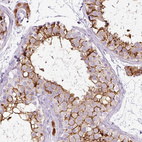

Immunohistochemical staining of human skin shows strong cytoplasmic positivity in melanocytes.